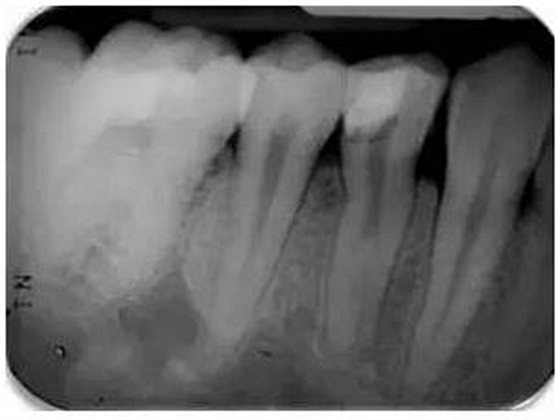

根尖周X線片必須要有最小的失真率和放大倍率,因?yàn)槿魏紊扉L(zhǎng)和透視縮短都會(huì)導(dǎo)致根管長(zhǎng)度測(cè)量的錯(cuò)誤。對(duì)牙根進(jìn)行仔細(xì)的評(píng)估是必不可少的,因?yàn)榭赡苡谢窝栏▓D1)。在中國(guó)患者中發(fā)現(xiàn)C形根管或其他蒙古人種特征的畸形牙根和根管是很常見(jiàn)的。因此,對(duì)X線片進(jìn)行全面評(píng)估以確定是否存在額外的牙根或根管是必要的,由此我們可以判斷治療的難度系數(shù)。